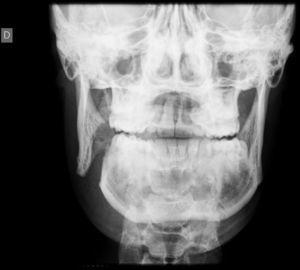

Se solicitó radiografía simple (Figura 1) que mostró fractura completa de rama mandibular derecha y fractura lineal parasinfisaria izquierda. Ante la no disponibilidad de ortopantomografía de urgencia se solicitó tomografía computarizada mandibular que evidenció fractura desplazada del ángulo mandibular derecho, con enfisema subcutáneo (Figura 2) y fractura parasinfisaria izquierda no desplazada.

Figura 1. Fractura completa de rama mandibular derecha y fractura lineal parasinfisaria izquierda en jugador de hockey hierba de 17 años con contusión facial directa.

Para el diagnóstico de las fracturas mandibulares, la radiografía panorámica u ortopantomografía proporciona una primera visión general muy aceptable, pero en muchos servicios de urgencias dicha prueba no está disponible. En estas situaciones, la radiología simple con proyección AP (Figura 1), Townes y oblicua lateral derecha e izquierda, generalmente permite visualizar la fractura, pero en caso de radiografía aparentemente normal y alta sospecha diagnóstica, se debería solicitar una tomografía computarizada mandibular (Figura 2). La tomografía computarizada es el estudio óptimo para la visualización de la mandíbula en todos los planos y, sobre todo, de los cóndilos. Estos frecuentemente están desplazados por la tracción de la musculatura masticatoria y se encuentran fuera de plano, por lo que en ocasiones las fracturas a este nivel pasan desapercibidas con pruebas radiológicas convencionales.